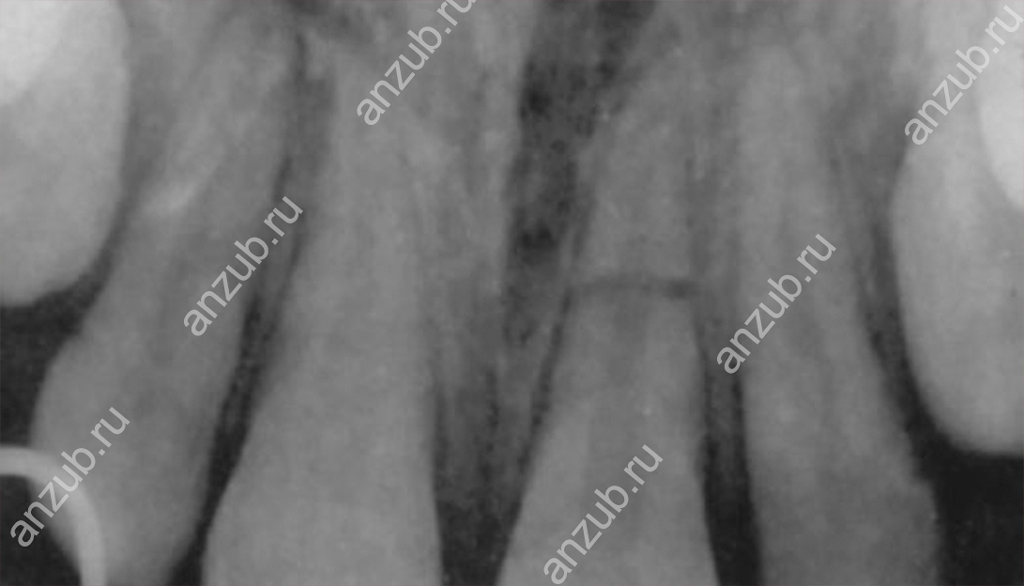

Наиболее информативным методом диагностики будет рентген или, лучше всего, компьютерная томография. С их помощью можно оценить не только место перелома и линию разлома, но и состояние окружающих тканей.

Различают несколько видов перелома:

- продольный, когда корень разломился на две части и разлом проходит по коронке тоже,

- поперечный, или горизонтальный разлом, когда отделяется верхушка или две трети,

- диагональный, или косой,

- множественные повреждения с образованием осколков.